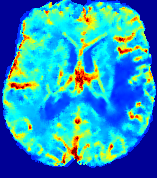

LesionRefer to captionRefer to captionRefer to captionRefer to captionRefer to captionRefer to caption𝐕rgbsubscript𝐕𝑟𝑔𝑏{\bf{V}}_{rgb}Refer to captionRefer to captionRefer to captionRefer to captionRefer to captionRefer to caption𝐕2subscriptnorm𝐕2{\|\bf{V}}\|_{2}Refer to captionRefer to captionRefer to captionRefer to captionRefer to captionRefer to captionRefer to caption3.53.53.52.82.82.82.12.12.11.41.41.40.70.70.70.00.00.0(mm/s)𝑚𝑚𝑠(mm/s)D𝐷DRefer to captionRefer to captionRefer to captionRefer to captionRefer to captionRefer to captionRefer to caption0.0200.0200.0200.0160.0160.0160.0120.0120.0120.0080.0080.0080.0040.0040.0040.0000.0000.000(mm2/s)𝑚superscript𝑚2𝑠(mm^{2}/s)Slice #1Slice #2Slice #3Slice #4Slice #5Slice #6

Figure 3: PIANO feature maps for one stroke patient, where the lesion is located in the left hemisphere. Top row: segmented stroke lesion region (white) on different slices, obtained from ISLES 2017. The corresponding slices for the PIANO feature maps are shown in the following rows.

For a better insight into an estimated velocity field 𝐕𝐕{\bf{V}} and diffusion field 𝐃𝐃{\bf{D}}, we compute the following maps: (1) 𝐕rgbsubscript𝐕𝑟𝑔𝑏{\bf{V}}_{rgb}: Color-coded orientation map of 𝐕=(Vx,Vy,Vz)T𝐕superscriptsuperscript𝑉𝑥superscript𝑉𝑦superscript𝑉𝑧𝑇{\bf{V}}=(V^{x},V^{y},V^{z})^{T}, obtained by normalizing 𝐕𝐕{\bf{V}} to unit length and mapping its 3 components to red, green, blue respectively; (2) 𝐕2subscriptnorm𝐕2\|{\bf{V}}\|_{2}: 222 norm of 𝐕𝐕{\bf{V}}; (3) D𝐷D: scalar field in Eq. 5.

Fig. 3 and Fig. 4 show the PIANO feature maps estimated from two ISLES 2017 patients: all are highly consistent with the lesion in both cases. Details of the blood flow trajectories are revealed in 𝐕rgbsubscript𝐕𝑟𝑔𝑏{\bf{V}}_{rgb} by the ridged patterns and the sharp changes of colors in the unaffected (right) hemisphere, while the flat patterns appearing within the lesion provide little directional information about the velocity and indicate low velocity magnitudes. Velocity magnitudes are more directly visualized via 𝐕2subscriptnorm𝐕2\|{\bf{V}}\|_{2}, from which one can easily locate the lesion where 𝐕2subscriptnorm𝐕2\|{\bf{V}}\|_{2} is low. D𝐷D also indicates lower diffusion values in the lesion, though with less contrast potentially due to the fact that it captures the accumulated effect of CA diffusion at the voxel-level.